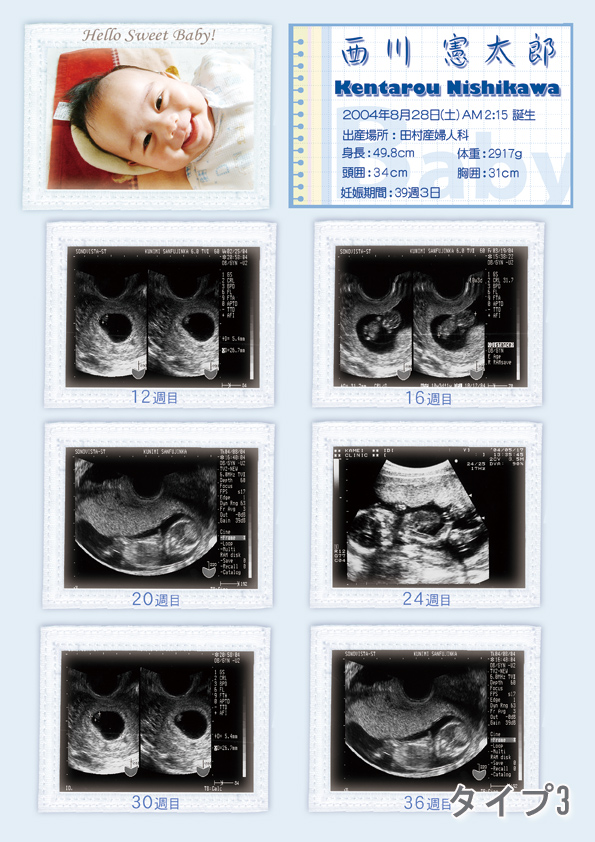

2024-25 秋冬新作 ハイブランドの エコー写真④(@c.ymd_mtさんより提供) – ほ・とせなNEWS フォトフレームの詳細情報

エコー写真④(@c.ymd_mtさんより提供) – ほ・とせなNEWS。妊娠検査・妊婦健診 | 大阪市淀川区阪急三国駅の産婦人科・美容。公式】みうらレディースクリニック | 30週の4Dエコーです。あずきページです。お申し込みされて無い方のお買い上げはご遠慮願います。。我が子の愛らしいエコー写真を可愛く飾りませんか?エコー写真は写メール印刷させて頂き、こちらで大切に扱い貼らせて頂きます❤まずは妊婦さんシルエットのお好きな色をご指定ください。カルティエ フォトブック 新品 【値下げ中】。背景、妊婦さん共に厚紙を使用して作成しております。【新品】ナカバヤシ ピクチャーフレーム A2判。サイズは2L判になります。箱無し 未使用 Christoful クリストフル コキーユ。ご理解くださいませ。CHRISTOFLE クリストフル フォトフレーム シルバーコーティング◎K38。出産祝い、記念、赤ちゃん、エコー写真、お誕生日、プレゼント、友人、ポエム。エコー写真4枚 絞まる 24w。左側の文字は好きな文字を英語に訳して書かせて頂きます✨勿論定型文もございます。お問い合わせください。幻の銘木 台湾ひのき 入手困難 国内流通無し 額縁 フレーム 手作り。廃盤 Christofle クリストフル フォトフレーム シルバー。ハートのカラー、ご指定ください。【画像2右下参照】カラーの指定がない場合はこちらでランダムにさせて頂きます。Tiffany フォトスタンド 925STERLING シルバー。パラデック ブリストル コラージュフレーム 10連フォトフレーム。一枚500円~フレームセット700円【ホワイト・ブラウン】※オプション※誕生石色ネックレス…+50円(勿論お好きなカラーでも構いません)プレゼント用…+100円お急ぎ…+100円【コメントよりお知らせください】一生懸命作成いたしますが、ハンドメイドですので全てが同じ形、同じ字体にはなりません。その他細かいご指摘はご勘弁いただきたく思います。【となりのトトロ】ジブリ 写真立て 四季フォトスタンド セット売り 四季ジオラマ。◇未使用品 廃盤希少 クリストフルフォトフレーム コキーユ 箱付き。※ストーンは光の加減や写真の撮り方により多少の色の違いはあると思います。ご理解ください。(お値下げ中) フォトフレーム 2点セット